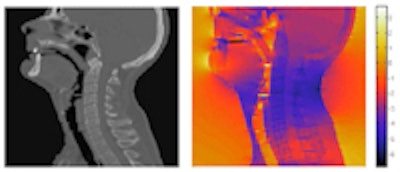

| CT of the head-and-neck area (left) and the magnetic field distribution in ppm of the nominal value (right). |

The researchers note that the image correction scheme could prove particularly valuable for imaging small radiotherapy targets within heterogeneous anatomies. In head-and-neck cases, for example, where tissue/air/bone transitions cause large field inhomogeneity, MR images recorded with a gradient strength of 1 mTm-1 can be distorted by as much as 9 mm.